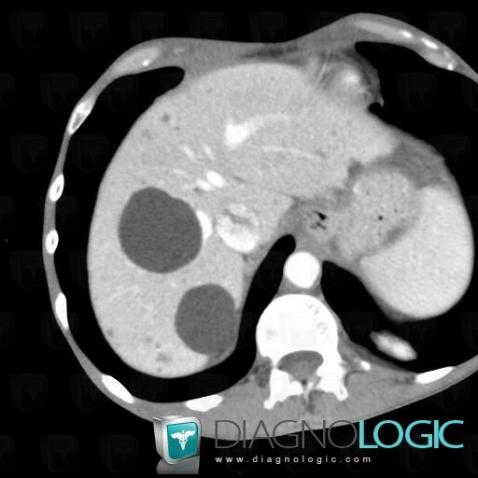

Kyste biliaire, Foie, Scanner

- Diagnostic Kyste biliaire, Localisation(s) Foie, comportant les gammes Lésion hypodense au temps portal, Lésion hépatique kystique